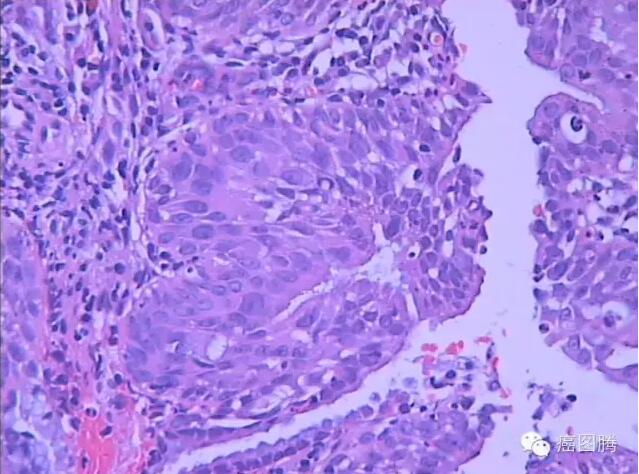

化生也称为“癌前病变”,是指一种已分化组织转变为另一种分化组织的过程,并非由已分化的细胞直接转变为另一种细胞,而是由具有分裂能力的未分化细胞向另一方向分化而成,一般只能转变为性质相似的细胞。机体的一种组织由于细胞生活环境改变或理化因素刺激,在形态和机能上变为另一种组织的过程,是机体的一种适应现象。如支气管黏膜的柱状上皮组织长期受刺激变为鳞状上皮组织。常见的化生有上皮化生、骨与软骨化生、浆膜化生、脂肪化生和骨髓化生。化生是局部组织在病理情况下的一种适应性表现,在一定程度上对人体可能是有益的。鳞状上皮的化生能增强粘膜的抵抗力,使粘膜在不利的情况下仍能生存。但支气管柱状上皮发生鳞状上皮化生时,丧失了纤毛,削弱了呼吸道的防御功能使易受感染。有时化生的细胞可以发生恶性肿瘤。如化生的鳞状上皮,有时未能分化成熟,产生不典型增生,可进而发生恶变,发生浸润成为鳞状细胞癌。胃粘膜的肠上皮化生与胃癌的发生可能有密切关系。